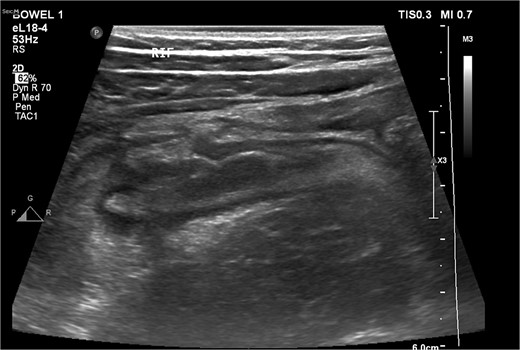

On examination, the patient was alert, oriented, and vitally stable. Abdominal examination revealed mild tenderness and rebound tenderness in the right iliac fossa. Laboratory investigations showed normal leukocyte counts and mildly elevated C-reactive proteins (38). An abdominal ultrasound suggested acute appendicitis or terminal ileitis (Fig. 1), prompting a CT scan despite the patient’s allergy to contrast.

An ultrasound picture showing tubular-like structure surrounded by edematous fluid.